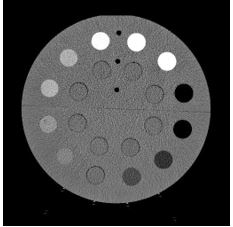

The goal of this study was to examine the feasibility and accuracy of a novel dual-energy CT technique in measuring the electron density. By using dual-layer CT (DLCT), the authors investigated two approaches to obtain relative electron densities. The results showed that DLCT-based electron density estimates have high validity and potential to improve the procedure and accuracy of measuring electron density in clinical practice.